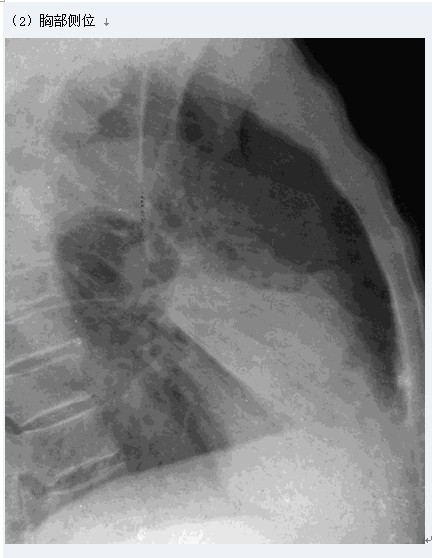

大叶性肺炎

图示为右肺中叶大叶性肺炎